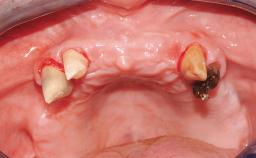

Conventional Loading of Eight Implants in the Maxilla and Final Restoration with a Full-Arch Gold-Ceramic FDP

A 35-year-old Caucasian female presenting with advanced periodontal disease involving both the maxillary and the mandibular dentition was referred for evaluation. The patient, a non-smoker in good general health, requested treatment for recurrent periodontal abscesses, tooth mobility, and discomfort during chewing, as well as restoration of her missing teeth with a fixed prosthesis to improve mastication and esthetics. All residual maxillary teeth exhibited plaque deposits, deep pockets, bleeding on probing, and class III mobility and were evaluated as hopeless. All residual mandibular teeth except tooth 37 could be maintained after periodontal therapy.